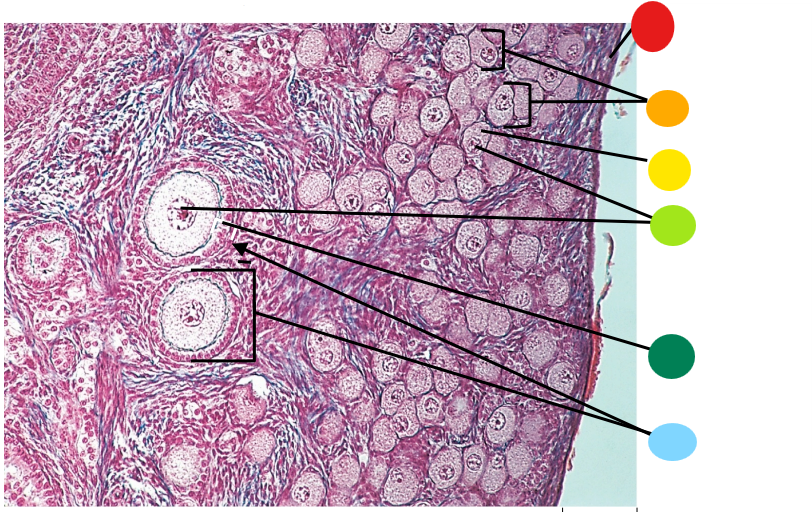

red

primordial follicles

red

primary follicles

red

tunica albuginea

orange

primary oocyte

yellow

primordial follicles

red

granulosa cells

orange

primary oocyte

what is this

primary follicle